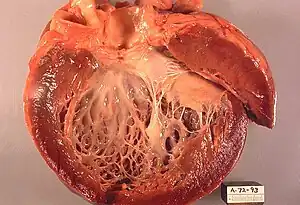

| Opened left ventricle showing thickening, dilatation, and subendocardial fibrosis noticeable as increased whiteness of the inside of the heart. | |